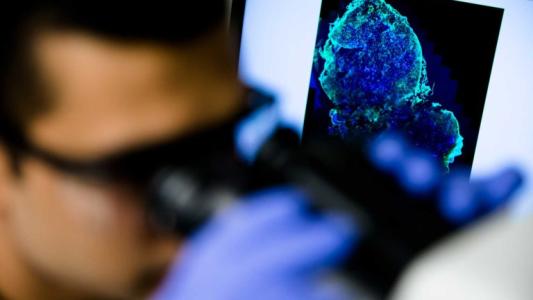

Glowing cancer cells could find hidden tumors (and replace mammograms)

A new pill can make cancer cells glow under infrared light, and it could eliminate for mammograms.